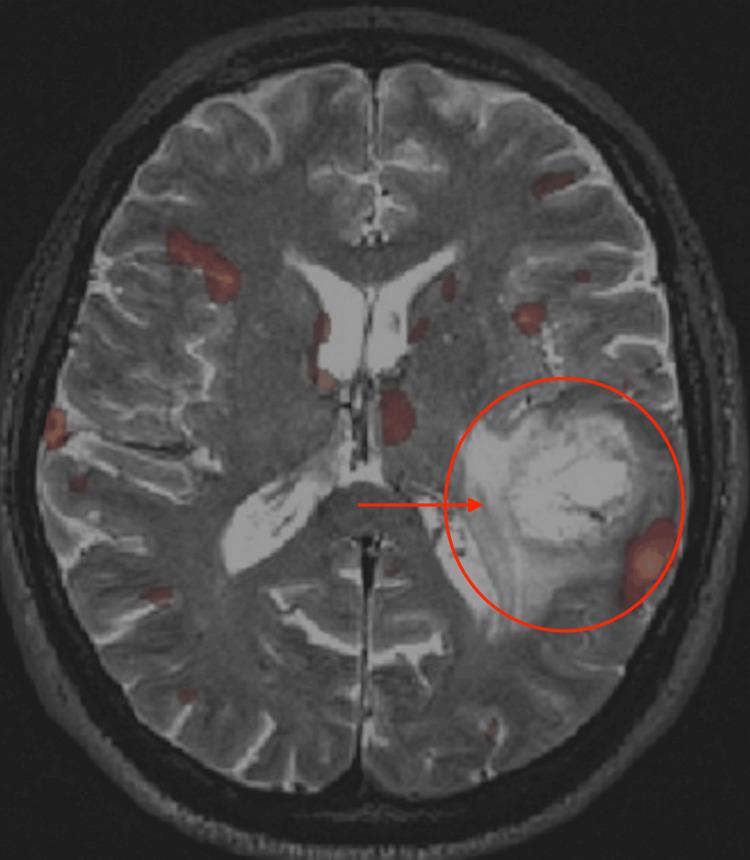

胶质母细胞瘤:治疗概述及磁共振波谱分析

Glioblastoma: Overview and Magnetic Resonance Spectroscopy Analysis for Treatment.

Glioblastoma multiforme (GBM) is a very aggressive and fast-growing cancer of the brain that has a low life expectancy. Many new cases are diagnosed every year with each having a very poor prognosis. It is therefore of utmost concern to develop cures for such a devastating condition. Magnetic resonance spectroscopy details certain peaks that are of interest. In particular, later-stage astrocytomas exhibit prominent choline and creatine peaks. The creatine peak is known to enhance glioblastoma survival.

多形性胶质母细胞瘤(GBM)是一种极具侵袭性且生长迅速的脑癌,患者预期寿命较短。每年都有许多新病例被诊断出来,每个病例的预后都非常差。因此,研发针对这种毁灭性疾病的治疗方法至关重要。磁共振波谱详细显示了某些感兴趣的峰。特别是,晚期星形细胞瘤表现出明显的胆碱和肌酸峰。已知肌酸峰可提高胶质母细胞瘤的生存率。